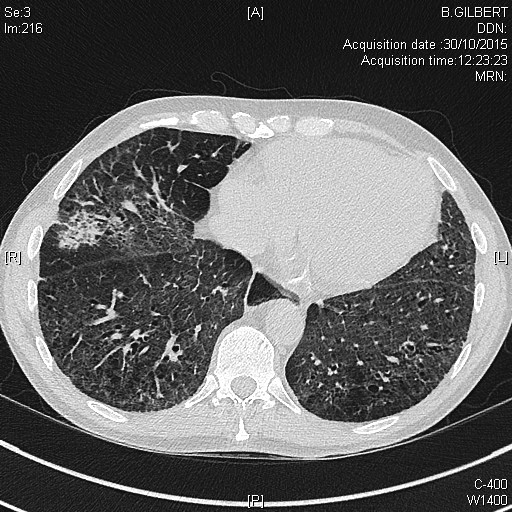

fibrose pulmonaire dans le cadre d'une sclérodermie systémique